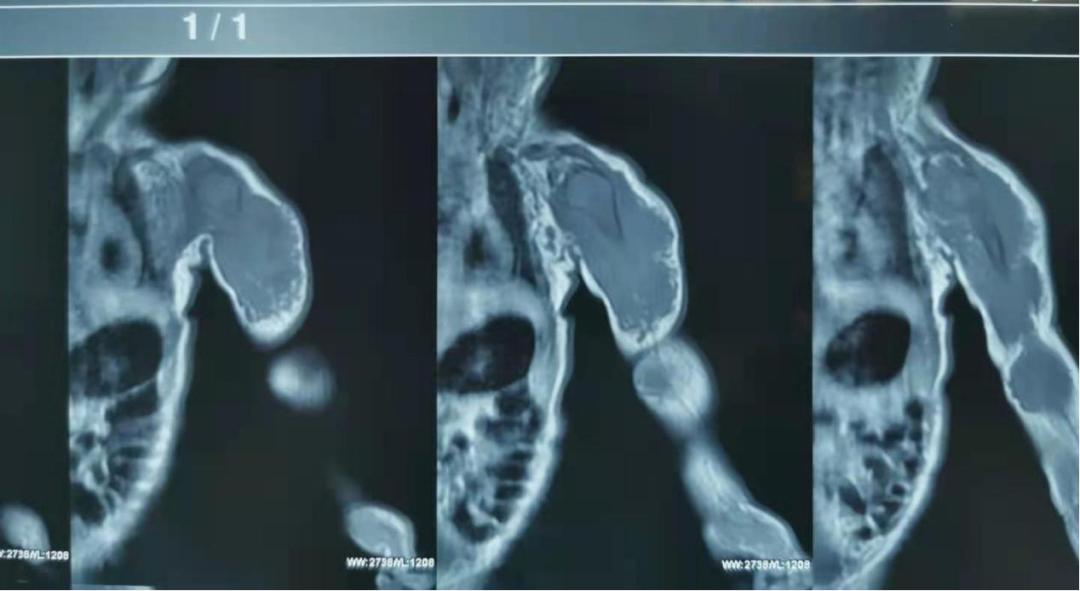

乔军波主任在大致了解情况后便对患儿进行查体,初步诊断该患儿是淋巴血管畸形,为尽快确诊并制定治疗方案,乔军波协调影像科完善患儿的核磁检查,结果显示: 这个巨大肿块样病变已经严重侵犯正常的神经、肌肉及肘关节囊,手术切除刻不容缓!

5月3日8点,这位患儿被送入手术室,在麻醉科与乔军波团队紧密配合下,手术顺利开始。术中可见,病变侵犯肘关节囊及桡神经,病变外侧紧贴桡神经、尺神经。